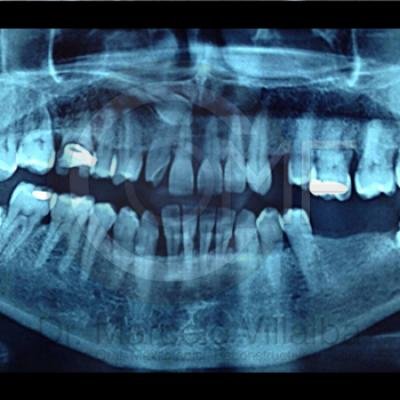

Generalmente en el momento de su erupción presentan procesos inflamatorios en la zona posterior de la cavidad oral, infección, dolor, movilidad de órganos dentarios, mal sabor en boca, mal olor en boca (halitosis), infección, incluso edema (aumento de volumen en tejido blando de la cara y/o boca) y complicaciones si no son atendidos. En el apoyo de diagnóstico se pueden requerir radiografías panorámicas y hasta tomografía en caso de ser necesarios.

Para el tratamiento de estas patologías se necesita en forma inicial estudios de laboratorio, radiografías o tomografías, estos estudios serán solicitados por el especialista a cada caso en particular, siendo su tratamiento quirúrgico bajo la modalidad de anestesia local o anestesia local más sedación consciente se puede realizar el procedimiento en corto tiempo y buen pronóstico.